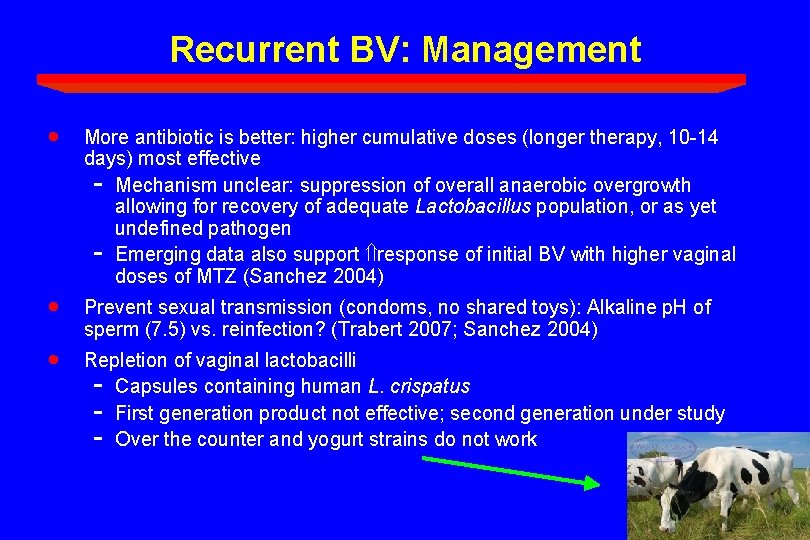

Recurrent BV: Management · More antibiotic is better: higher cumulative doses (longer therapy, 10 -14 days) most effective - Mechanism unclear: suppression of overall anaerobic overgrowth allowing for recovery of adequate Lactobacillus population, or as yet undefined pathogen - Emerging data also support response of initial BV with higher vaginal doses of MTZ (Sanchez 2004) · Prevent sexual transmission (condoms, no shared toys): Alkaline p. H of sperm (7. 5) vs. reinfection? (Trabert 2007; Sanchez 2004) · Repletion of vaginal lactobacilli - Capsules containing human L. crispatus - First generation product not effective; second generation under study - Over the counter and yogurt strains do not work